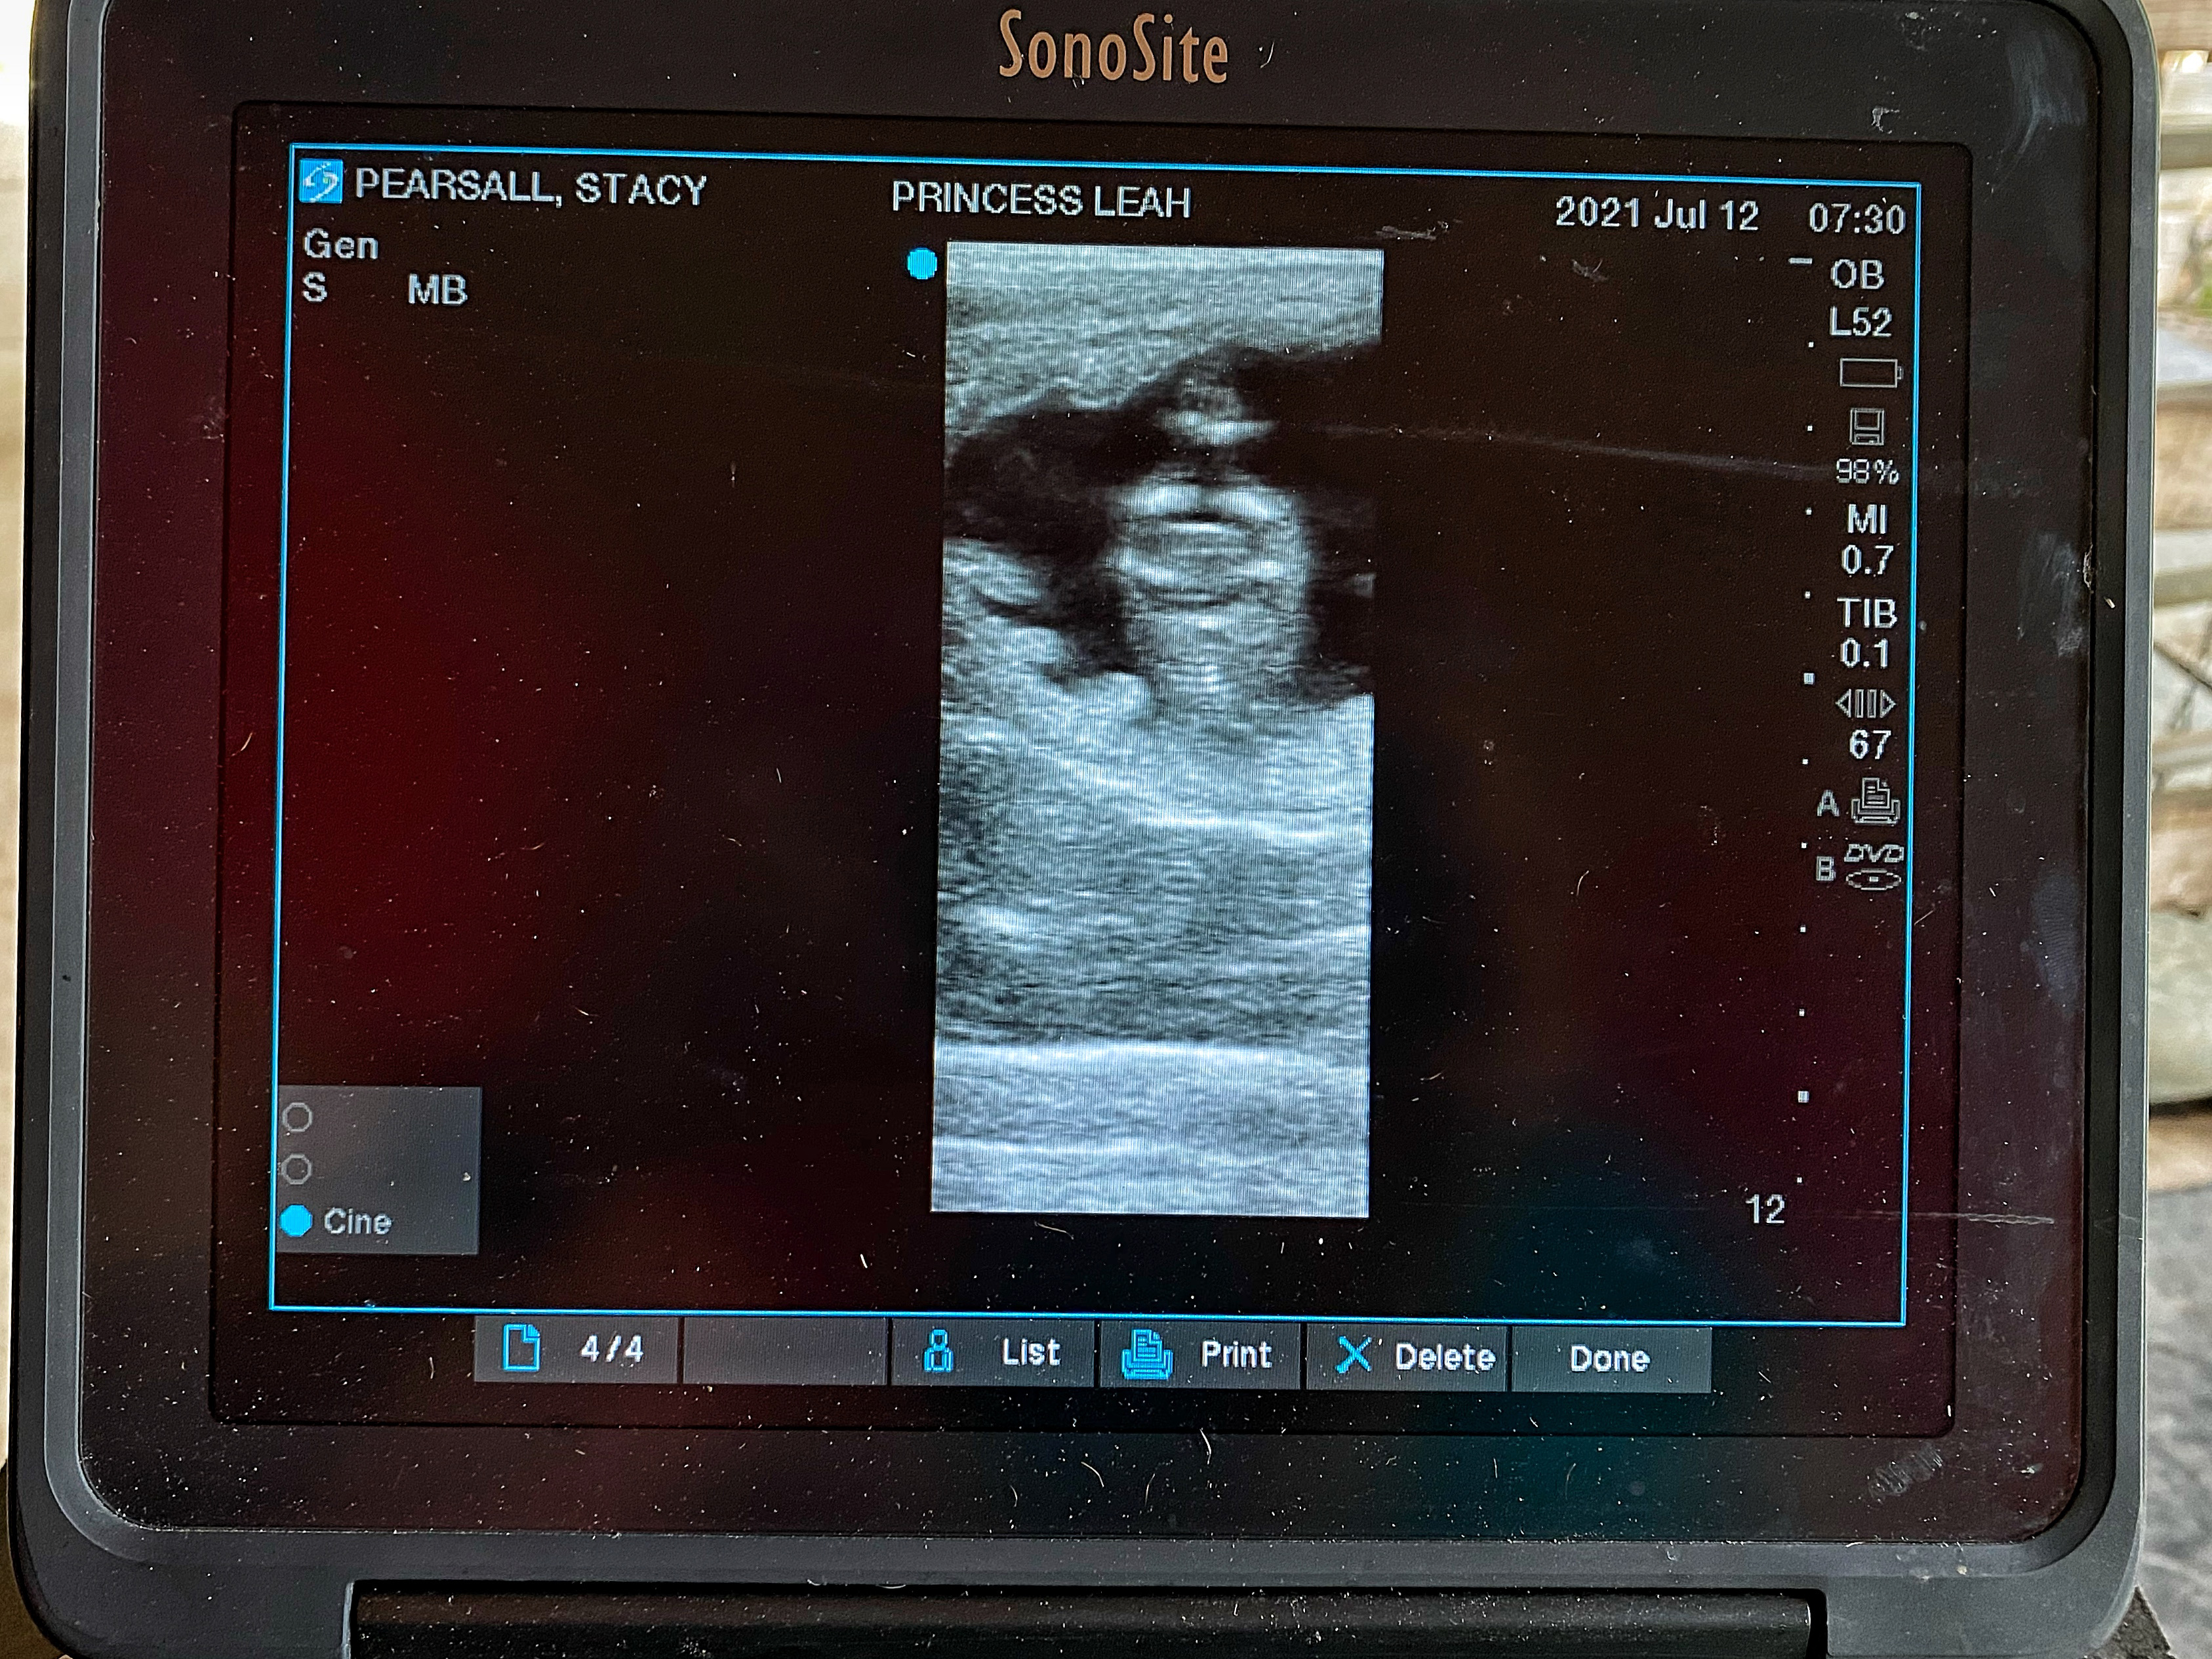

On-sight Artificial Insemination